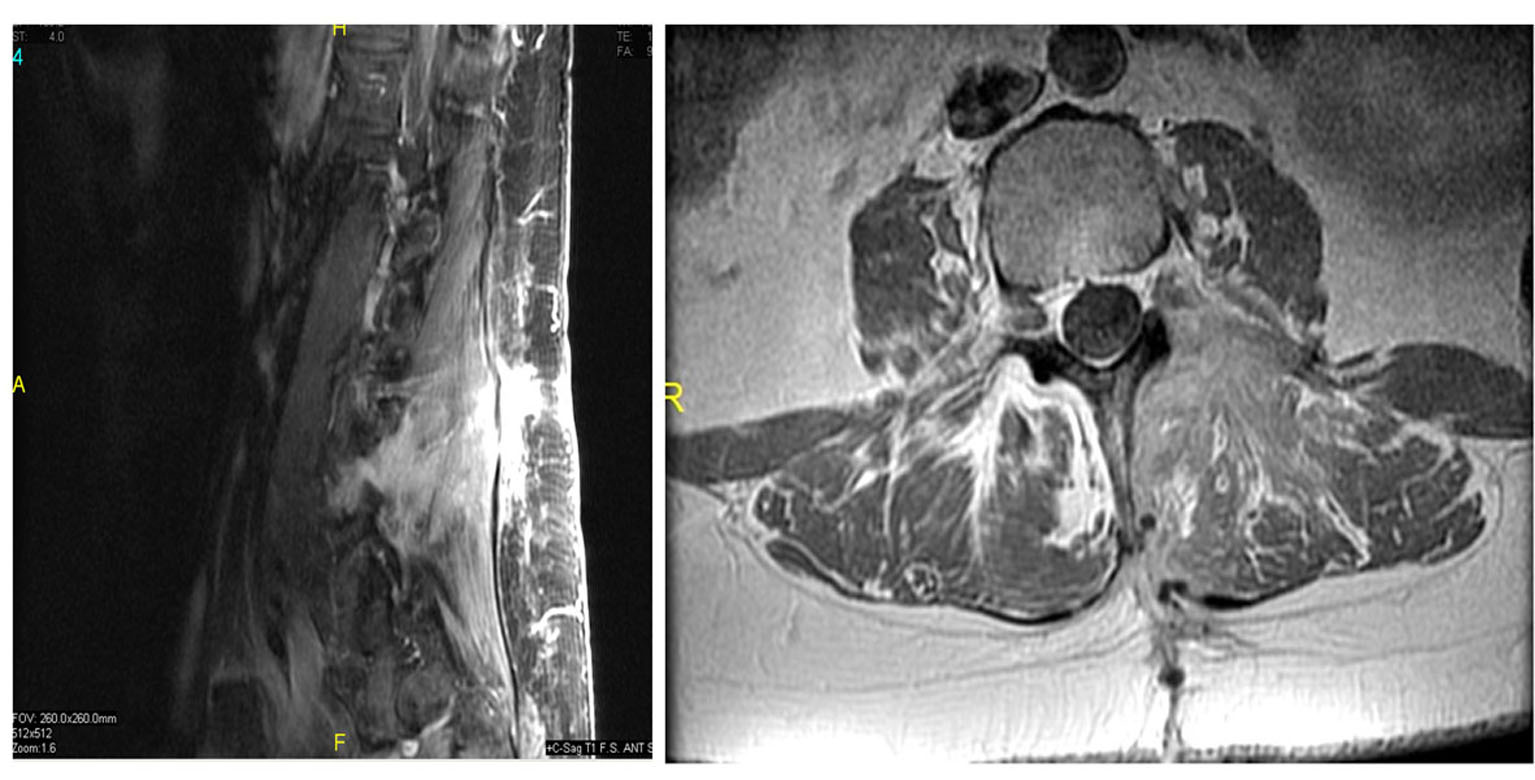

A review of imaging studies of the lumbar spine with and without contrast showed a variable enhancing lesion with what appears to be some fluid levels in a multilobulated lesion of the left L4 neural foramen that was read by the radiologist as a hemangioma or possible nerve sheath tumor (Fig. 1). She has had imaging studies as recently as 3 years ago which she reported did not show any abnormality in the lumbar spine.

Click for large image | Figure 1. Preoperative T1 sagittal (right) and axial (left) MRI with contrast showed a variable enhancing lesion with possible fluid levels in a multilobulated lesion of the left L4 neural foramen. |